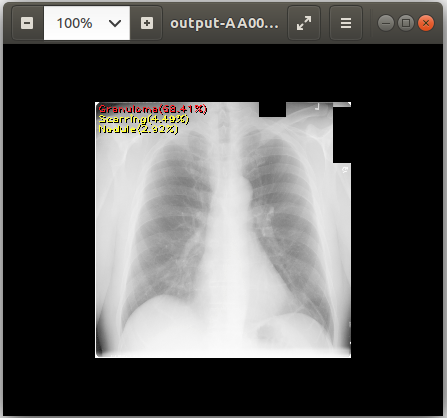

cat output-AA0007572607123433_v2.csv # View text output eog output-AA0007572607123433_v2.png # View image output using `eog` which is an image viewer available in Ubuntu

chest_xray_example_output1.png